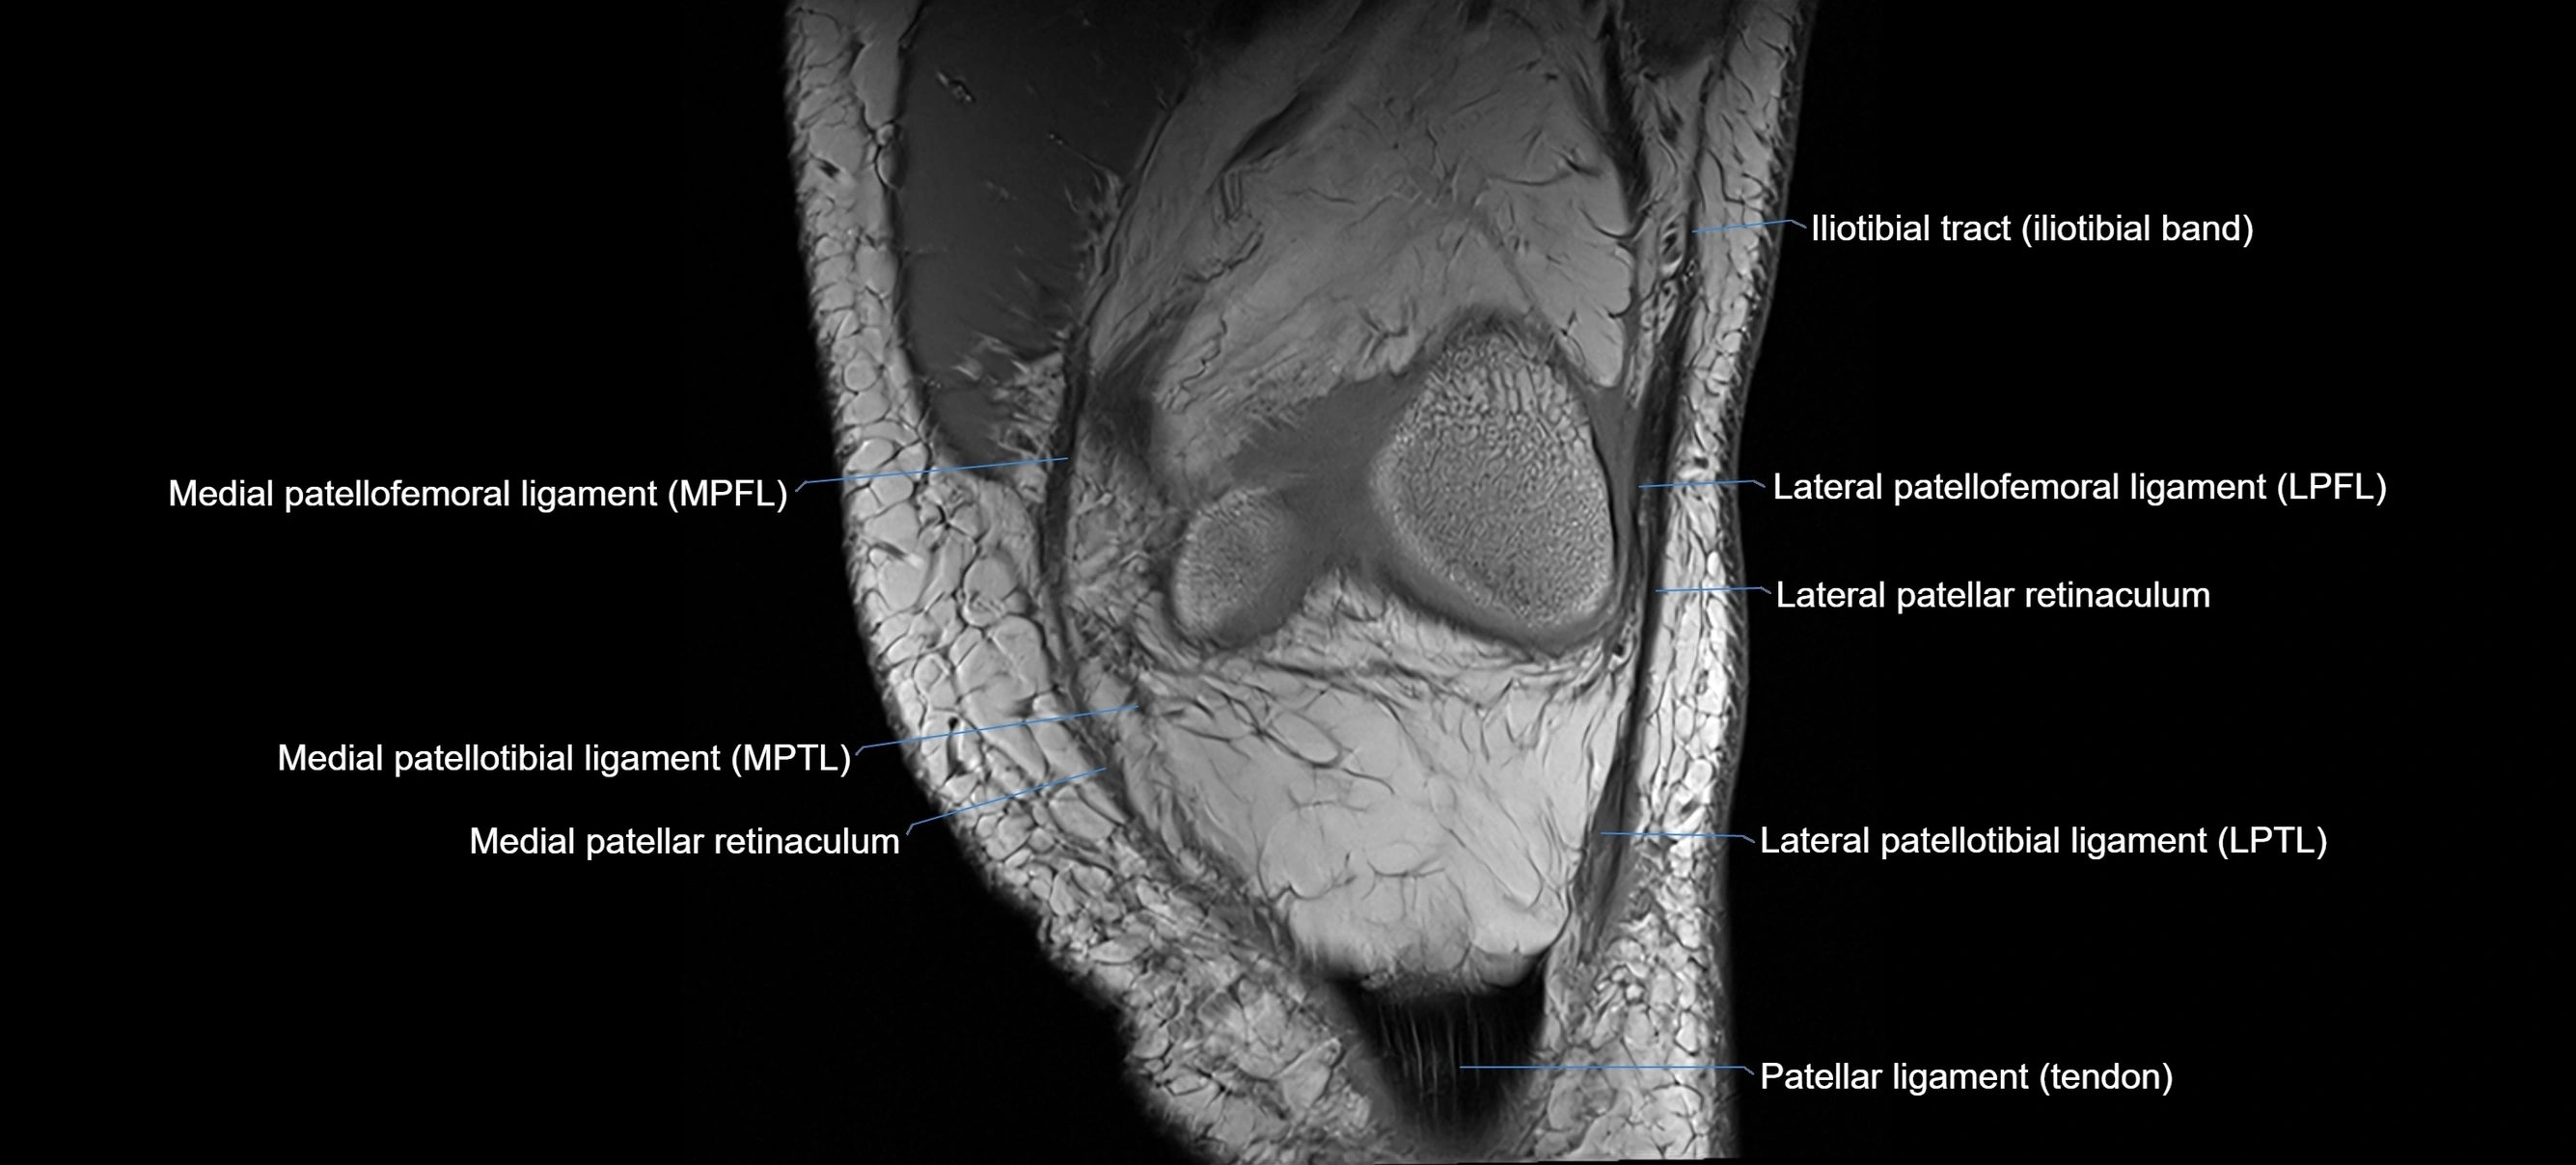

MRI images

image